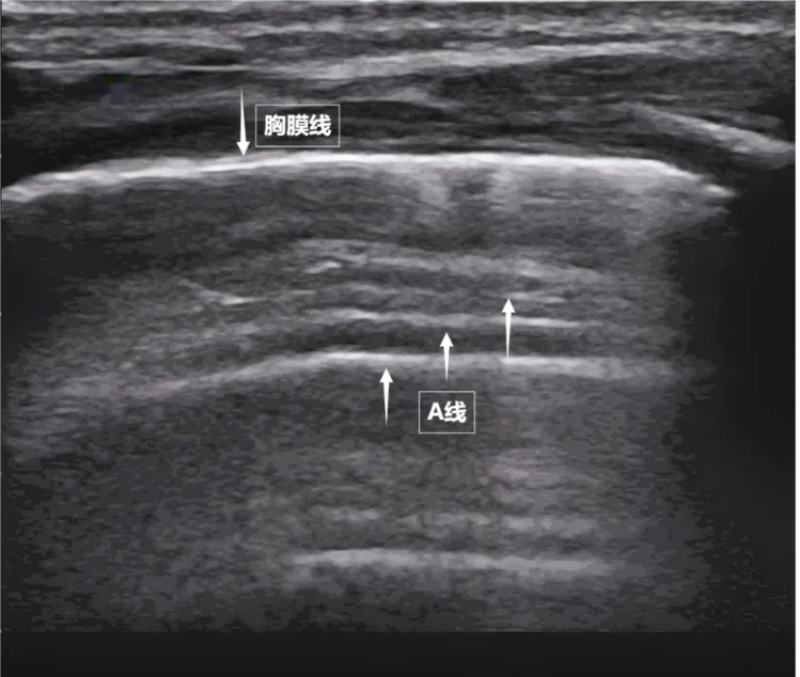

第一景:“海岸线与海浪”——胸膜线与A线

当声波穿过胸壁肋骨缝隙,首先会遇到紧贴肺表面的光滑薄膜——壁层胸膜和脏层胸膜。两者紧密相贴,中间没有多余的气体或液体。它们在屏幕上呈现为一条明亮、光滑的水平线,共同构成了胸膜线。这条线就是肺的“海岸线”。在它的下方,由于肺泡内大量气体对声波的强烈反射,会出现一系列与胸膜线平行的、等间距的、重复出现的明亮平行线,像海浪般不断向屏幕深处延伸,这就是A线(见下图)。A线是正常含气肺部的典型标志。它的存在直接提示肺表面含气充足,胸膜腔内无异常积液或气体。

图为正常新生儿肺部超声表现